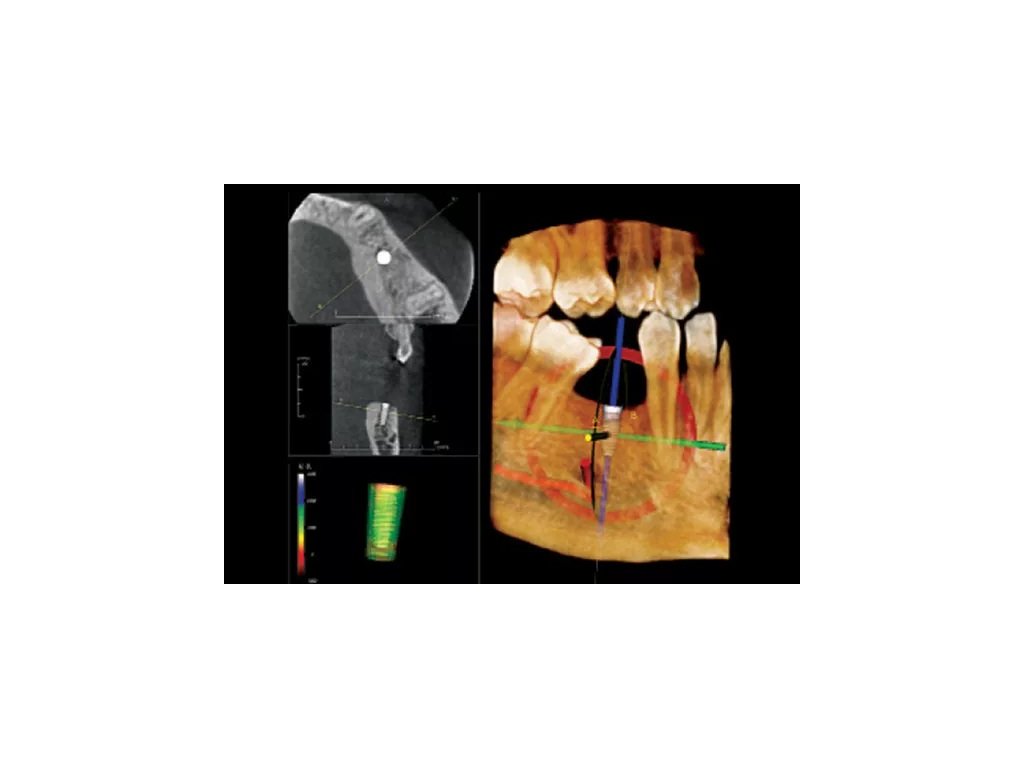

Endo zobrazení nabízí komplexnější zobrazení vnější i vnitřní struktury, tedy i vizualizaci pulpy nebo přímá vizualizace kořenového kanálku. Můžete si tedy jednodušeji zobrazit vnitřní morfologii kanálku, včetně zakřivení kořenů, jejich počet a lokalizaci vstupů kořenových kanálků. V endodontické vizualizaci můžete také provádět přesná měření.